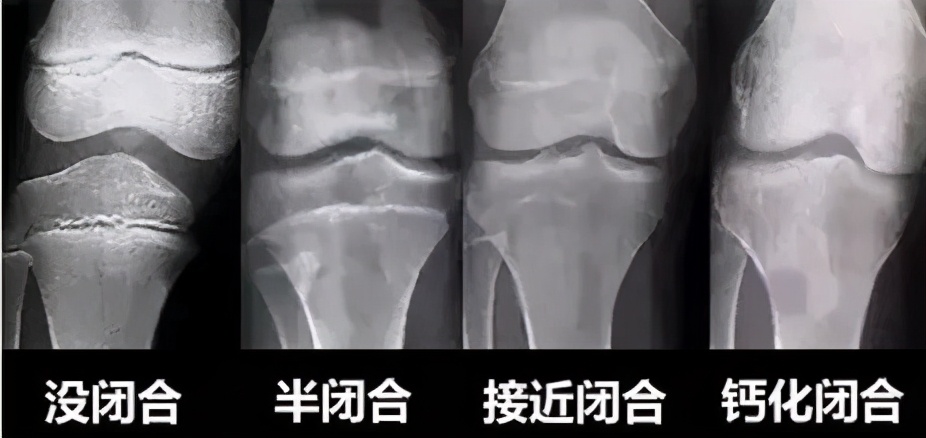

但如果你是个成年人,而且骨骺已经闭合了,无论怎么跳绳,都不可能再长高了!